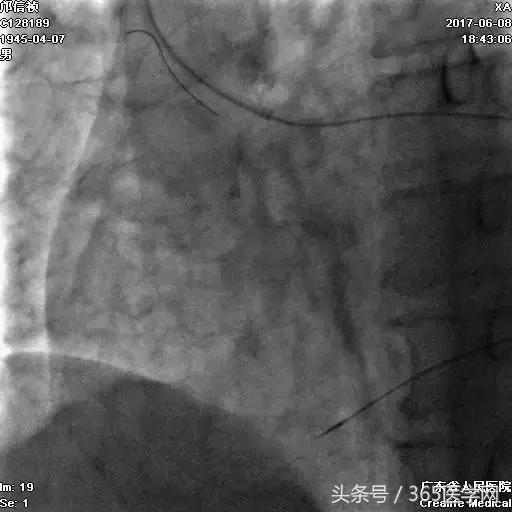

RCA闭塞段球囊扩张后IVUS

支架术后造影结果

支架术后IVUS